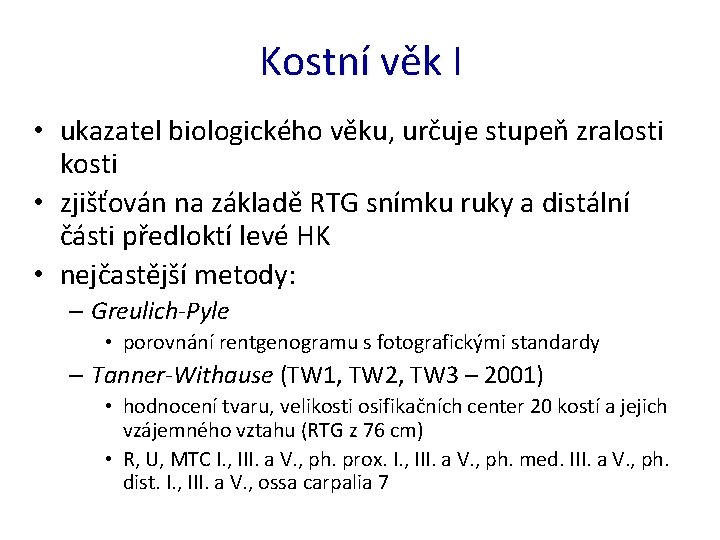

Kostní věk I • ukazatel biologického věku, určuje stupeň zralosti kosti • zjišťován na základě RTG snímku ruky a distální části předloktí levé HK • nejčastější metody: – Greulich-Pyle • porovnání rentgenogramu s fotografickými standardy – Tanner-Withause (TW 1, TW 2, TW 3 – 2001) • hodnocení tvaru, velikosti osifikačních center 20 kostí a jejich vzájemného vztahu (RTG z 76 cm) • R, U, MTC I. , III. a V. , ph. prox. I. , III. a V. , ph. med. III. a V. , ph. dist. I. , III. a V. , ossa carpalia 7